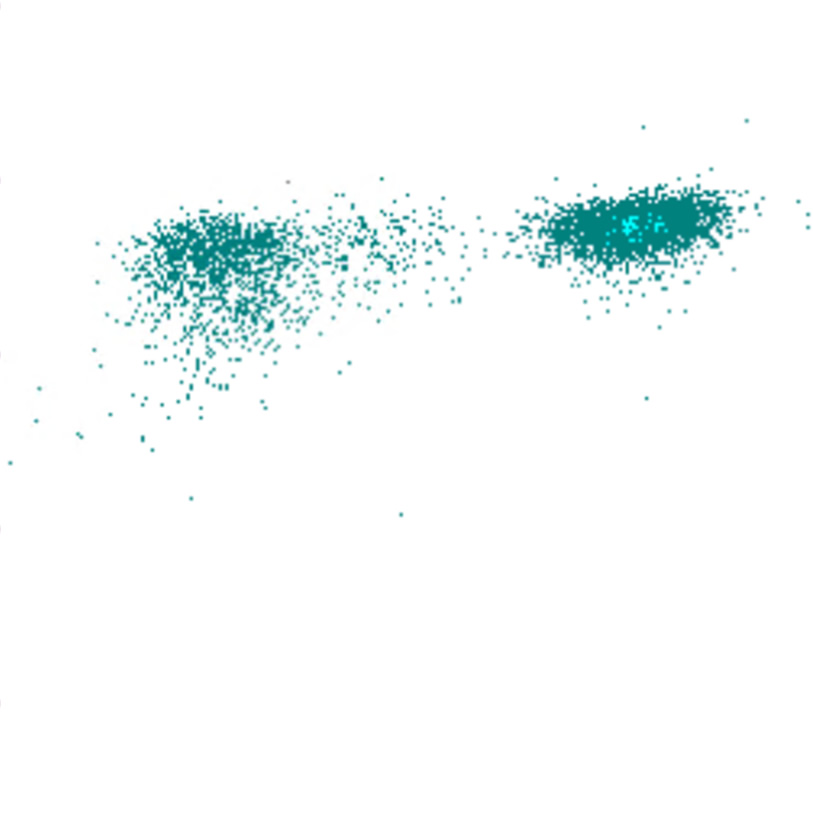

Side Fluorescence

Le signal SFL reflète la teneur en acides nucléiques des cellules. Les cellules avec un SFL élevé contiennent davantage d’ARN et/ou d’ADN, ce qui indique souvent une activité ou une prolifération accrue. Il existe une corrélation limitée entre le SFL et le FSC ; bien que les cellules plus grandes présentent généralement un SFL plus élevé, des exceptions existent, telles que des blastes avec un SFL relativement faible ou des lymphocytes activés avec un SFL élevé malgré leur plus petite taille.

SFL scatter

SFL faible

SFL élevé